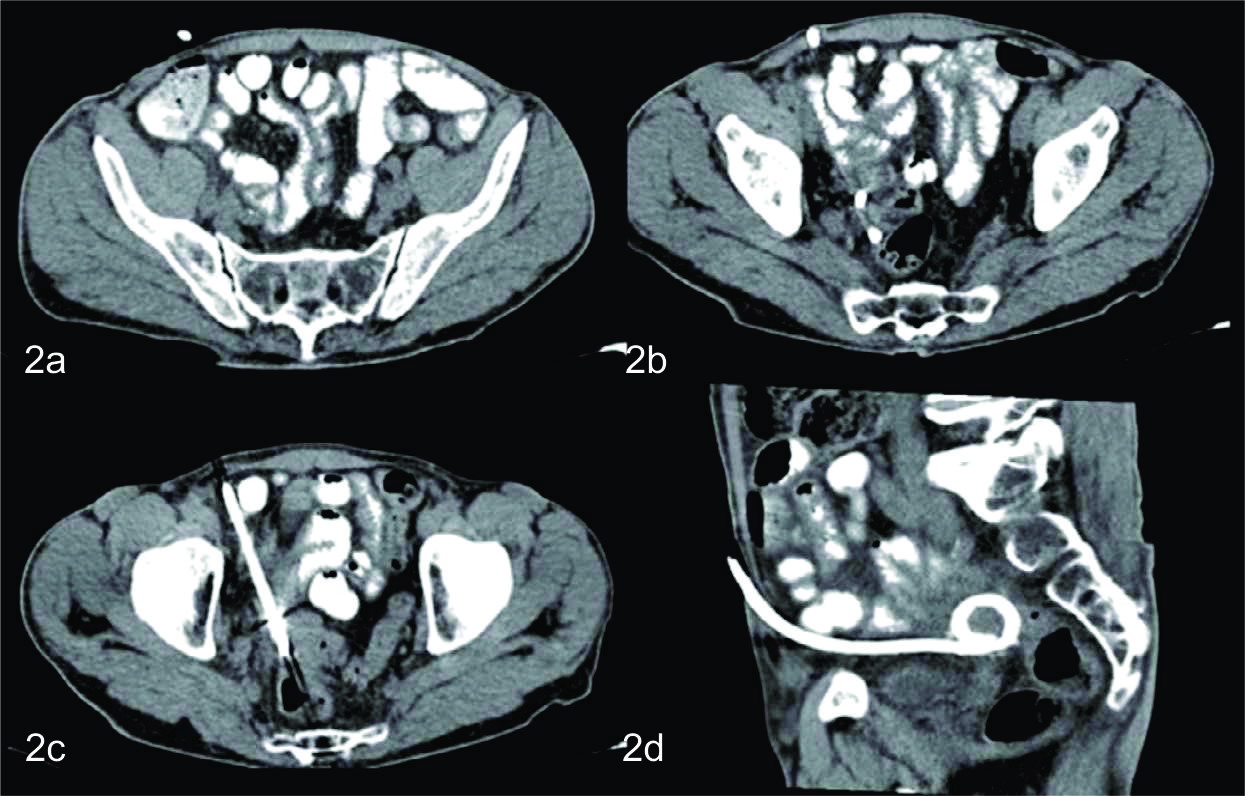

En el control tomográfico posterior, realizado a los 7 días del procedimiento, se reconoce el catéter de drenaje ingresando por la pared anterior del abdomen, el cual se dirige caudomedial con su extremo en el fondo de saco de Douglas, sin evidencia de colección residual. Se decide realizar prueba terapéutica cerrando el drenaje. Dada la buena evolución, el mismo es retirado a las 48 hs.

En los cortes más caudales se reconoce al ciego en su topografía habitual y de él se observa emerger de su pared posterior, al apéndice cecal, el cual es de aspecto patológico, tomando contacto con la colección antes descripta. Con el planteo de apendicitis aguda complicada con colección infectada se discute junto con cirujano tratante la eventual posibilidad de poder realizar tratamiento percutáneo, el cual se determinó que era pasible de ser efectuado en este paciente. Se realizó nuevamente bajo guía tomográfica con el paciente en decúbito supino. Se procedió a topografiar el sitio de abordaje en piel a nivel de flanco derecho y se coloco drenaje multipropósito 12 F bajo técnica de Seldinger, el cual se dejo abierto a bolsa colectora con llave de tres vías. El material obtenido fue purulento, algo hemorrágico, con grumos, del cual se tomaron muestras para análisis bacteriológico, cultivando gérmenes gram negativos. En el control tomográfico posterior, a los cinco días de colocado el drenaje, se necesitó un reposicionamiento del mismo, pudiendo evacuar totalmente la colección residual en la evolución. Luego de 15 días de colocado el drenaje, con levados diarios en los últimos 7 días, una vez resuelta la colección, sin elementos clínicos ni paraclínicos humorales de infección, se decide retirar el drenaje, presentando el paciente una excelente evolución.

Ambos pacientes tuvieron una excelente evolución, otorgándoles el alta hospitalaria a los 10 días aproximados del día de la consulta en puerta de emergencia, sin la necesidad de realizar en ninguno de ellos una apendicectomia electiva, debido a su buena evolución.